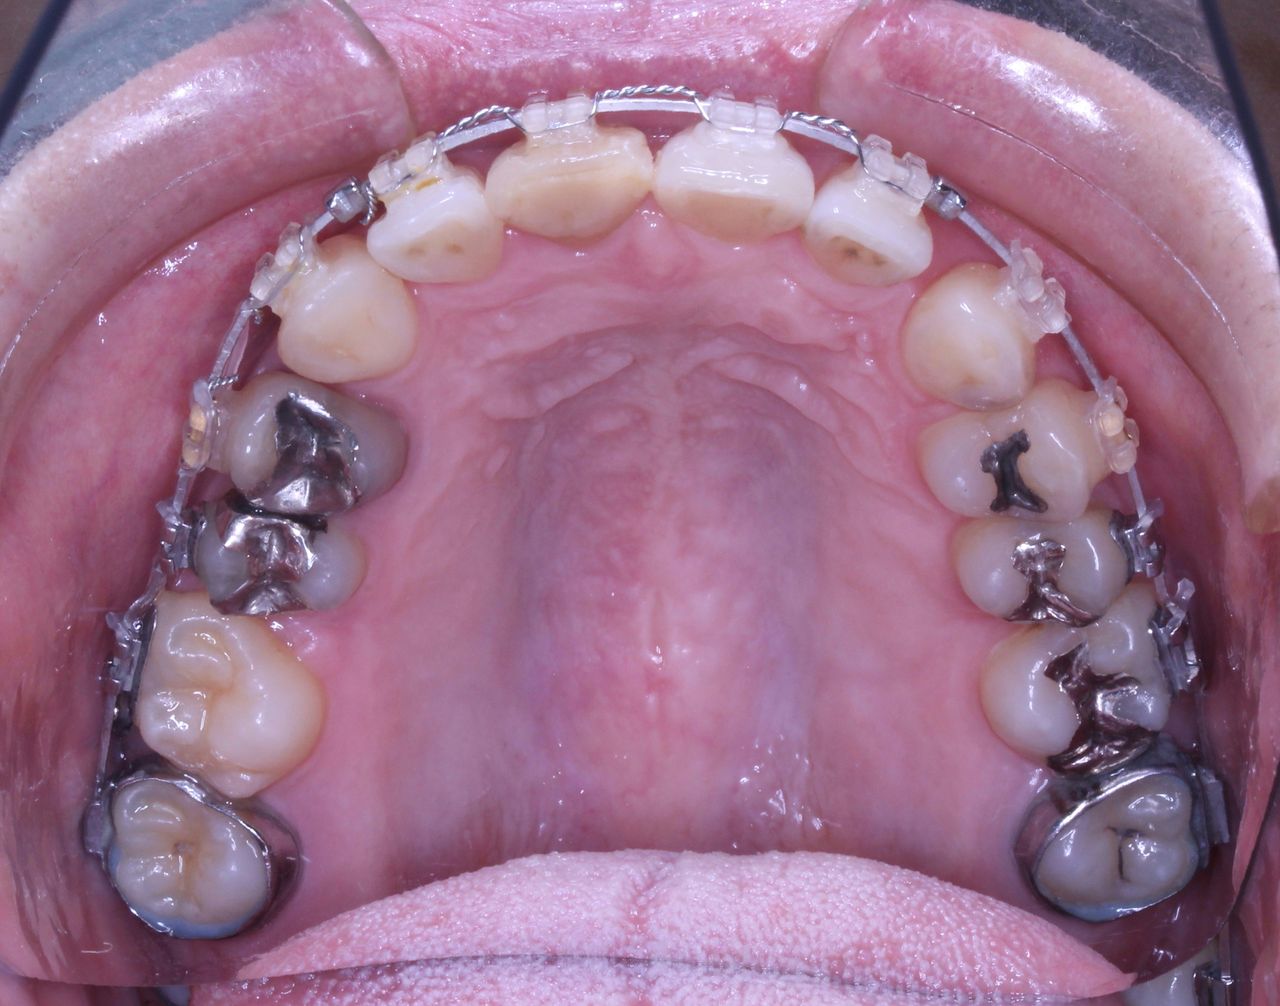

虫歯治療はきちんとされてますが、奥歯に全部銀歯の状態の歯があります。

当然、神経もない歯です。治療されたのはだいぶ前とのことでした。

それでは治療経過です

少し経過が進みました